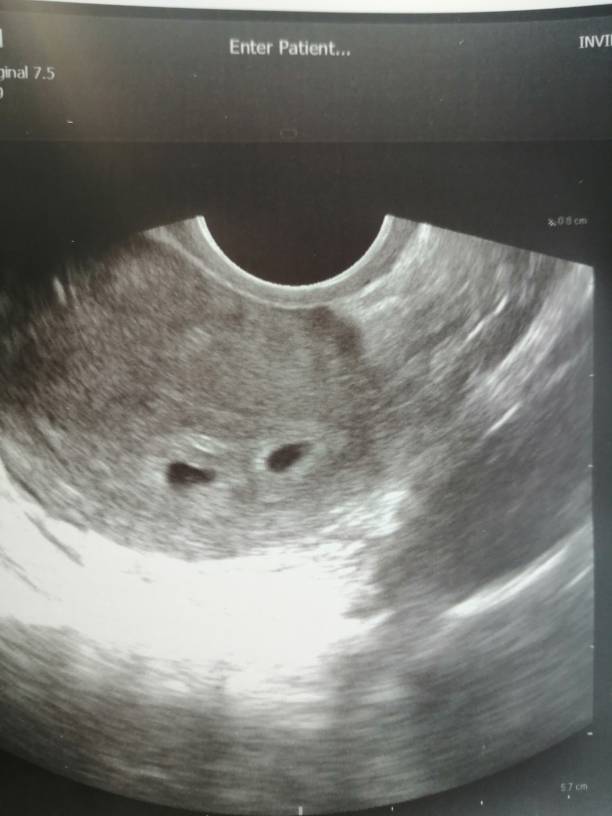

Już są pierwsze blizniaki na forum

IMG_20200228_081819.jpeg